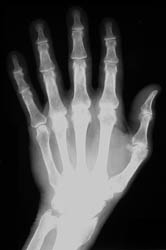

Commonly affected sites of the hands include the metacarpal heads, especially

at the 2nd and 3rd metacarpophalangeal joints, and the interphalangeal and

carpal joints. .

Osseous eburnation, joint space narowing, well-defined subchondral cysts,

radial beak-like osteophytosis at the metacarpal heads, and osteoporosis are

all radiographic findings which are frequently seen in this disease process.

Chondrocalcinosis is seen in up to fifty percent of the cases, with a direct

correlation noted between the amount of chondrocalcinosis and the degree of

arthropathy.